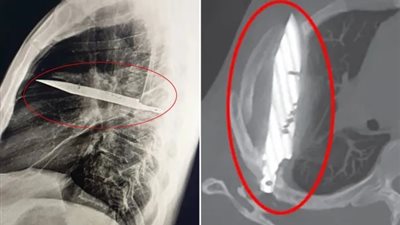

بعد شعوره بالألم.. أطباء يعثرون على سكين عالقة في صدر شخص منذ 8 سنوات